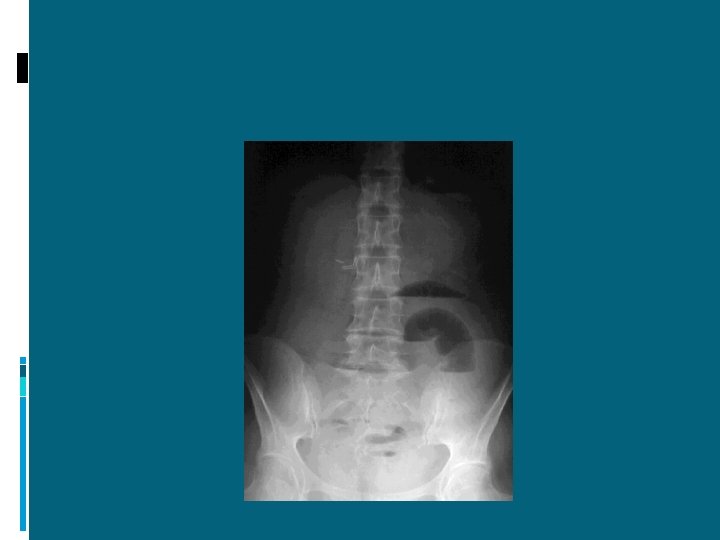

ILEO MECCANICO: SINTOMATOLOGIA Dolore Vomito Chiusura dell’alvo a feci e gas Distensione addominale Segni di disidratazione

ILEO MECCANICO: DIAGNOSI ESAME OBIETTIVO: ISPEZIONE: Distensione addominale Ricerca di ernie Ricerca di cicatrici laparotomiche

ILEO MECCANICO: DIAGNOSI RX DIRETTA ADDOME IN ORTOSTATISMO: presenza di livelli idroaerei